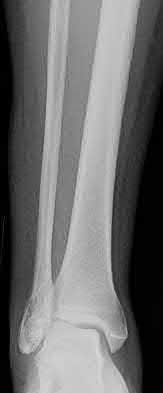

The safe zone for tibial nail placement as seen on radiographs is just medial to the lateral tibial spine on the anteroposterior radiograph and immediately adjacent and anterior to the articular surface as visualized on the lateral radiograph.

Tornetta et al specifically located the safe zone for nail entry in a study using fresh frozen cadaver knees. The authors found that the safe zone for nail placement is located 9.1+/-5 millimeters lateral to the midline of the plateau and three millimeters lateral to the center of the tibial tubercle. The width of the safe zone averaged 22.9 millimeters and was as narrow as 12.6 millimeters.

The starting point of the of the nail can be best viewed on the lateral knee radiograph, an example of which is shown in Illustration A. Illustration B shows the "sweet spot" for nail insertion as defined by Tornetta.